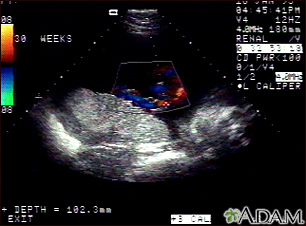

Ultrasound, color - normal umbilical cordBackUltrasound, color - normal umbilical cordThis is a normal color Doppler ultrasound of the umbilical cord performed at 30 weeks gestation. The cord is the colored area in the middle of the screen, with the different blood vessels represented by different colors. There are normally three vessels in the cord, two arteries and one vein. The umbilical cord is connected to the placenta, located in the middle left of the image. E-mail FormEmail ResultsName:Email address:Recipients Name:Recipients address:Message: